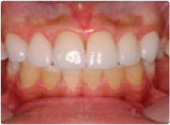

メタルセラミックスとオールセラミックスの比較

治療前

治療後

術前、術後で白丸部分の歯肉の色の変化を比べてみれば分かると思いますが、メタルセラミックスよりオールセラミックスは、歯肉の色が明るくより自然です。 これは、メタルセラミックスでは、中のメタルが外からの光を遮断してしまうためで、アンブレラ効果といわれているもののために起こります。